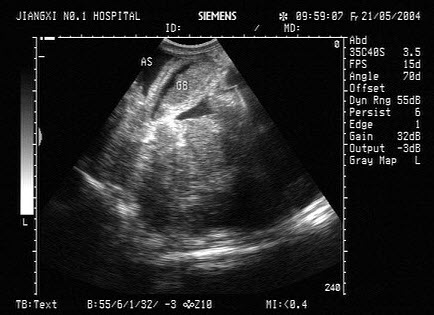

18、单项选择题

女,26岁,停经3个月,HCG阳性。根据B超检查声像图如下,最可能的诊断为()

A.葡萄胎

B.子宫肌瘤

C.稽留流产

D.不全流产

E.绒癌